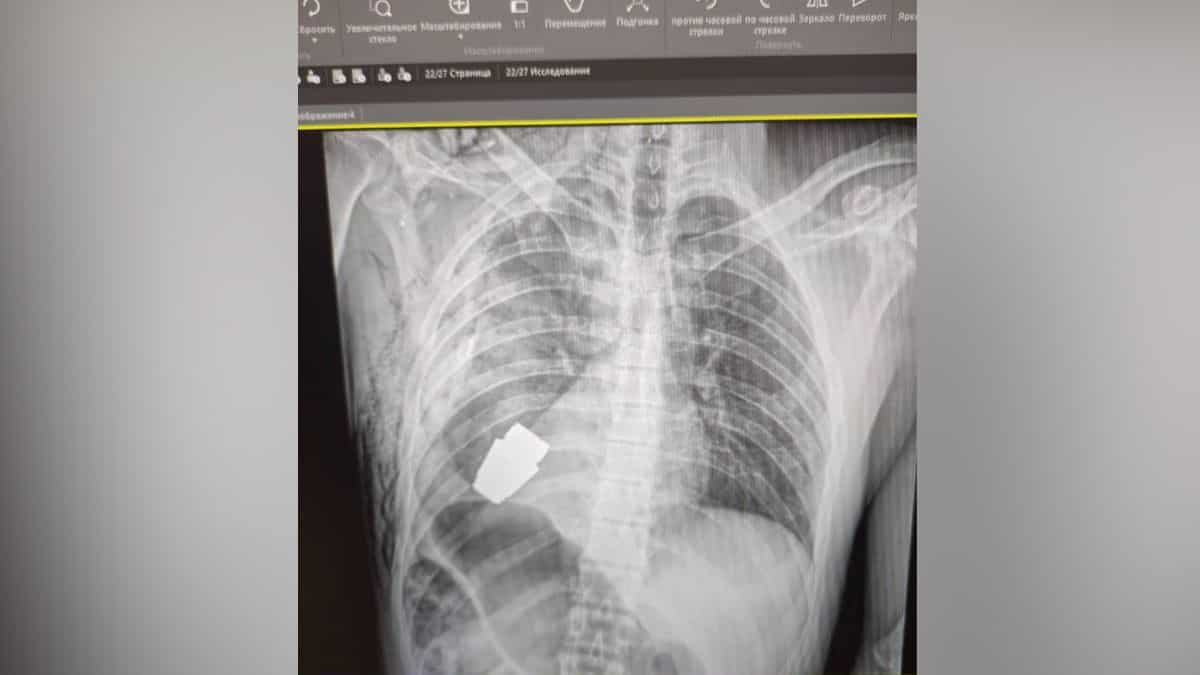

The unexploded weapon was removed from just beneath the heart of the injured military man. Ukraine's deputy minister of defence Hanna Maliar uploaded an image that showed the X-ray image attributed to the operated-upon soldier.

"Military doctors conducted an operation to remove a VOG grenade, which did not break, from the body of the soldier," she wrote in a Facebook post.

Internal affairs minister Anton Gerashchenko wrote in a Telegram update early on Thursday: "The unexploded part of the grenade was taken from under the heart. The grenade did not explode, but remained explosive."